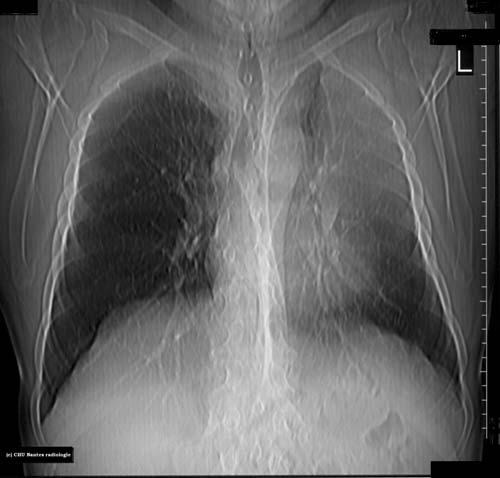

Atélectasie